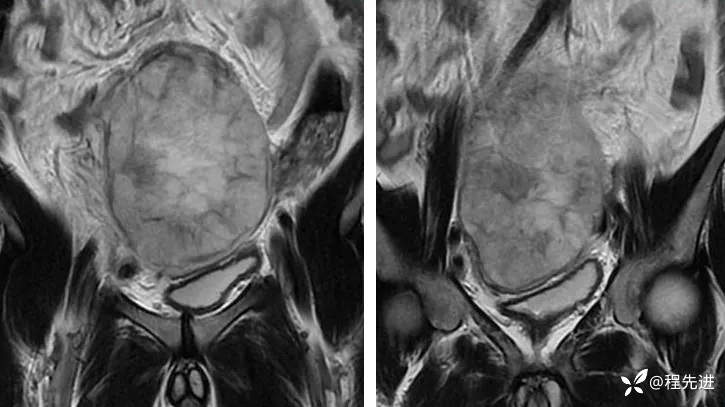

【腹盆】特别精彩病例|下腹痛20余天,男性病人腹腔巨大肿块该如何诊断

【患者信息】:男,41岁

【主诉】:下腹痛20余天

既往史:隐睾

肿瘤标志物:甲胎蛋白(AFP)>10000

增强: